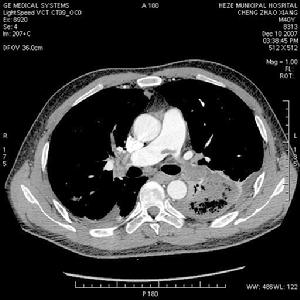

脂肪栓塞綜合徵1肺部表現

發生率約75%。開始於缺氧導致的呼吸急促及隨後的過度換氣,紫紺有時不會出現,但有時可能成為FES的早期體徵。涉及肺的FES病人大部分PaO2水平低於6.67kPa,如果肺的條件惡化,就可能合併呼吸困難和代謝性酸中毒。部分病人有咯血。胸部X線片示兩肺大塊斑片狀陰影,稱之為“暴風雪樣”改變,尤其在肺的上中部多見。

脂肪栓塞綜合徵--X線1呼吸支持療法不完全型或部分症候群:可以鼻管或面罩給氧,使氧分壓維持在9.3-10.7kPa(70-80mmHg)以上即可,創傷後3-5天內應定時血氣分析和胸部X線檢查。